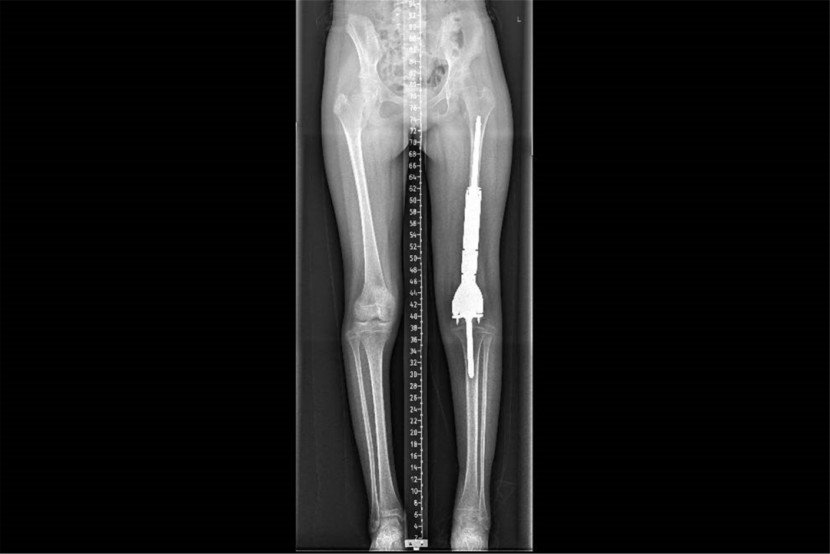

这是小鱼的术前CT影像

小鱼的股骨下段肿瘤长达15厘米、宽度达6.5厘米,王克及其团队制定了“新辅助化疗+保肢手术”的个体化方案。经过4个月8次高强度化疗,其肿瘤宽度从6.5厘米缩小至3.5厘米,腿围由38厘米降至33厘米,为后续保肢手术创造了关键条件。

这是小鱼的术后X线影像